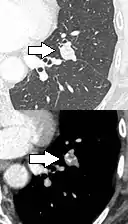

Lung nodule abutting a pulmonary cyst.[9]

• A lung nodule abutting a pulmonary cyst is a rare finding, yet indicating cancer.[9]